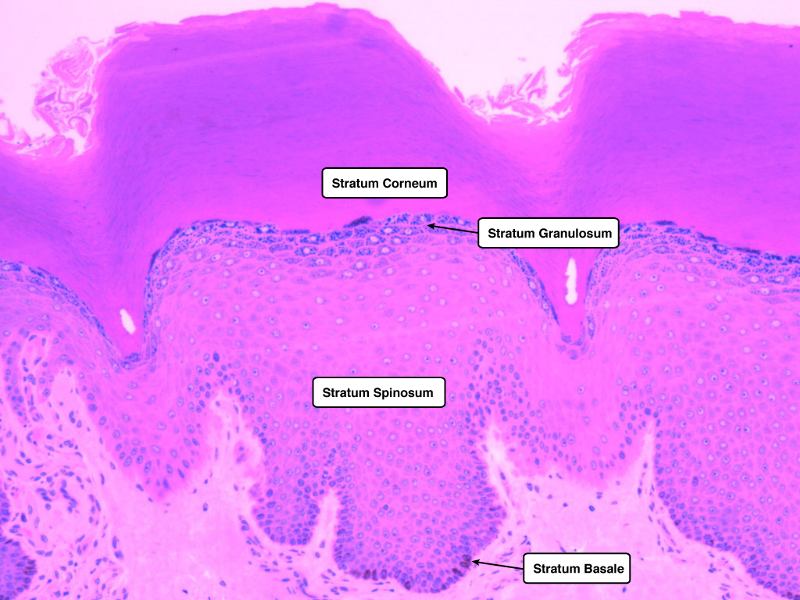

Skin

Consider a needle penetrating skin.

Describe the layers.

Up to and including the vein.

List the layers

Which layers of cells are penetrated?

What do they look like?

What is the function of each layer?

What is the function of each type of cell?